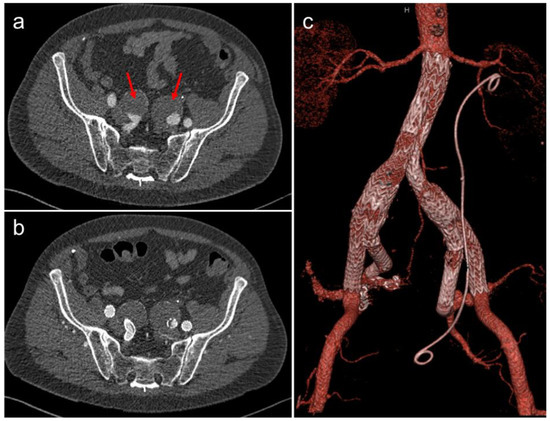

3.4. Endovascular Repair of Aortoiliac Aneurysms